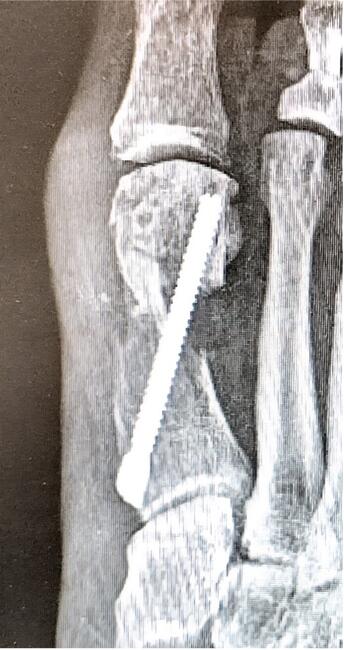

The second type of metatarsal explosion is identified by a pathognomonic “double metatarsal sign.” This explosion pattern is a complete through-and-through fracture of the first metatarsal. The fracture is split into 2 pieces along the transverse plane, extending into the tarsometatarsal joint, creating an illusion of 2 metatarsals on an AP radiograph. The prevalence of this type of metatarsal explosion is 31%.7 Figure 1 displays a Type 2 metatarsal explosion.

The third type of metatarsal explosion is the most catastrophic, identified by a large detached “butterfly fragment.” The Type 3 explosion has multiple fracture fragments that travel along the plane of fixation, similar to Type 2 explosions, but is extra-articular and does not exit the first metatarsal-cuneiform joint. The fragments form a dorsal butterfly fragment that is the hallmark appearance of this fracture type. Type 3 is the rarest at 19% and the most often requiring revision surgery.7

One of the main factors associated with metatarsal explosions was felt to be technique driven; either placing the screw too close to the osteotomy, in the case of Type 1 explosions, or inserting the screw at an angle excessively dorsiflexed or plantarflexed, as seen in the other explosion types. However, the complication also occurred in the setting of flawless technique. Despite being an uncommon complication, it is thought to be an inevitable one. There was no significant difference in preventing metatarsal explosions between 1- and 2-screw techniques.7